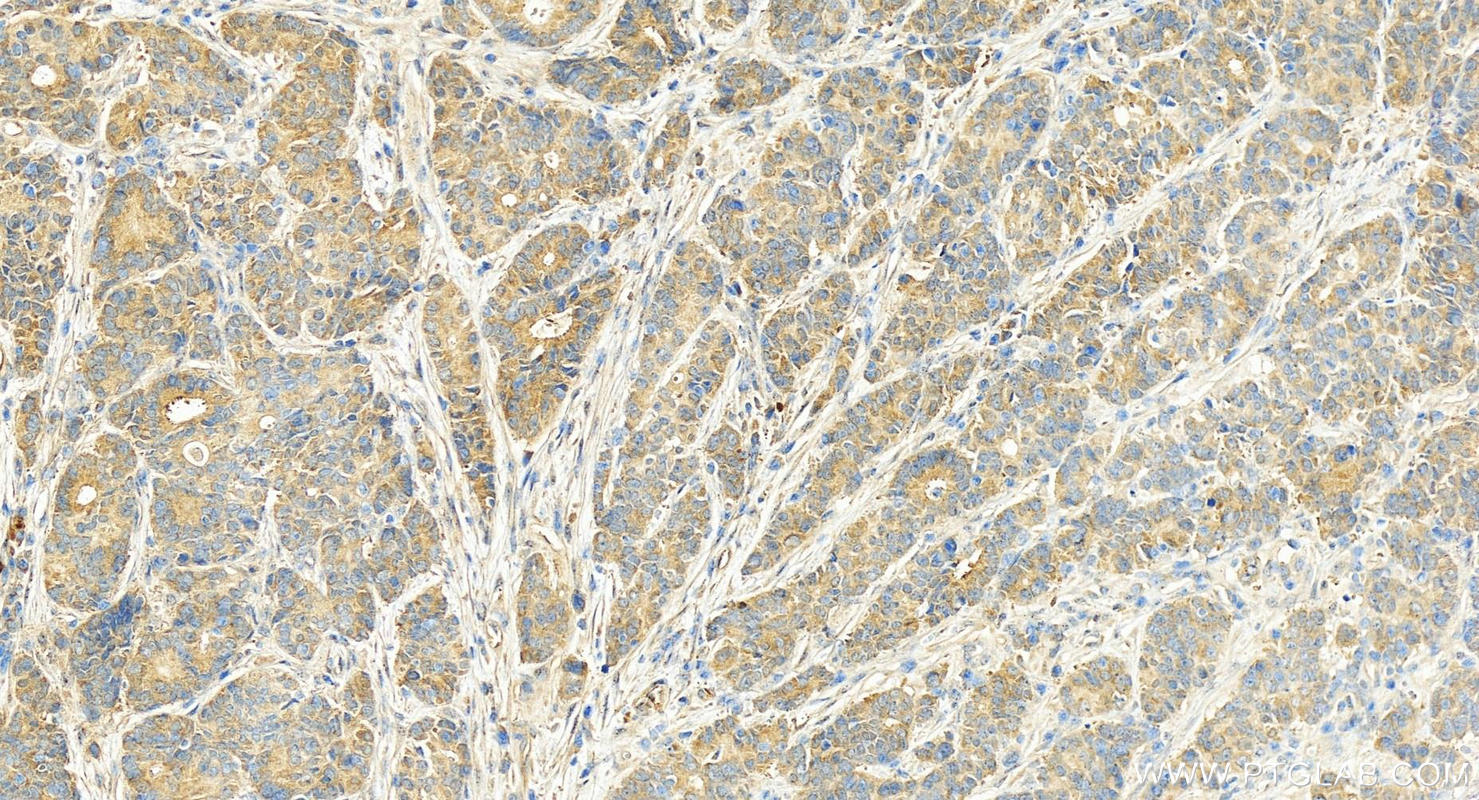

| Positive IHC detected in | human stomach cancer tissue Note: suggested antigen retrieval with TE buffer pH 9.0; (*) Alternatively, antigen retrieval may be performed with citrate buffer pH 6.0 |

| Immunohistochemistry (IHC) | IHC : 1:50-1:500 |